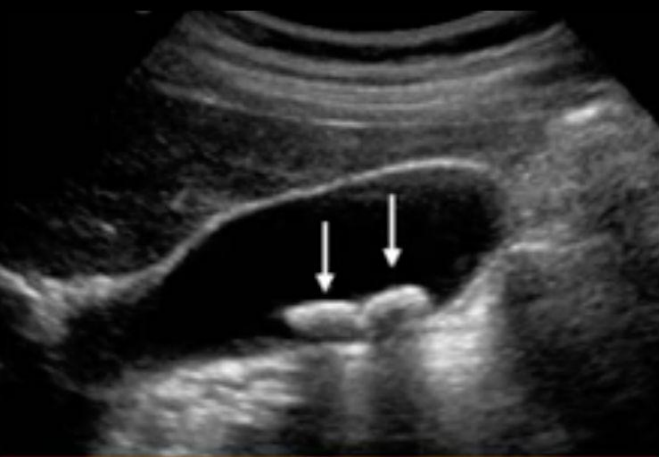

¿Qué signo ecográfico es típico de litos vesiculares?

Sombra sónica posterior (HIPERECOGENICIDADES)